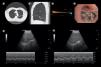

Quantitative CT (QCT) thorax confirmed upper lobe-predominant, heterogeneous emphysema with an intact fissure (98% completeness over right oblique fissure and 100% completeness over right horizontal fissure) over the right lung (Fig. 1, Panel A & B). Pre-procedure, right-hemi diaphragmatic excursion measured 3.35cm with a sniff maneuver in 45° semi-recumbent position (Fig. 1, Panel E). Under total intravenous anesthesia, three endobronchial valves were placed in the segmental bronchi of the right upper lobe after confirming no collateral ventilation (Fig. 1, Panels C & D). Post-procedure, pneumothorax occurred within 24h, necessitating an intercostal chest drain for 10 days. Patient was discharged uneventfully.

High-resolution CT thorax showing upper lobe predominant heterogeneous emphysema with centrilobular distribution in the right lung (Panel A) and complete fissure integrity (Panel B). Absence of collateral ventilation confirmed by occlusion of the right upper lobe ostium with the Chartis® balloon (Panel C). Deployment of three endobronchial valves in the anterior, posterior, and apical segments of the right upper lobe (Panel D).

Two weeks post-procedure, right hemi-diaphragmatic excursion increased to 4.50cm (+34%) (Fig. 1, Panel F; Video 1). A follow-up chest radiograph at one month showed complete collapse of the right upper lobe, accompanied by improvements in FVC (+1.05l), FEV1 (+0.50l), RV (−2.12l), and a significant increase in 6MWT distance (+280m). Clinically, the patient's mMRC scale improved to one, and he could engage in moderate physical activity.